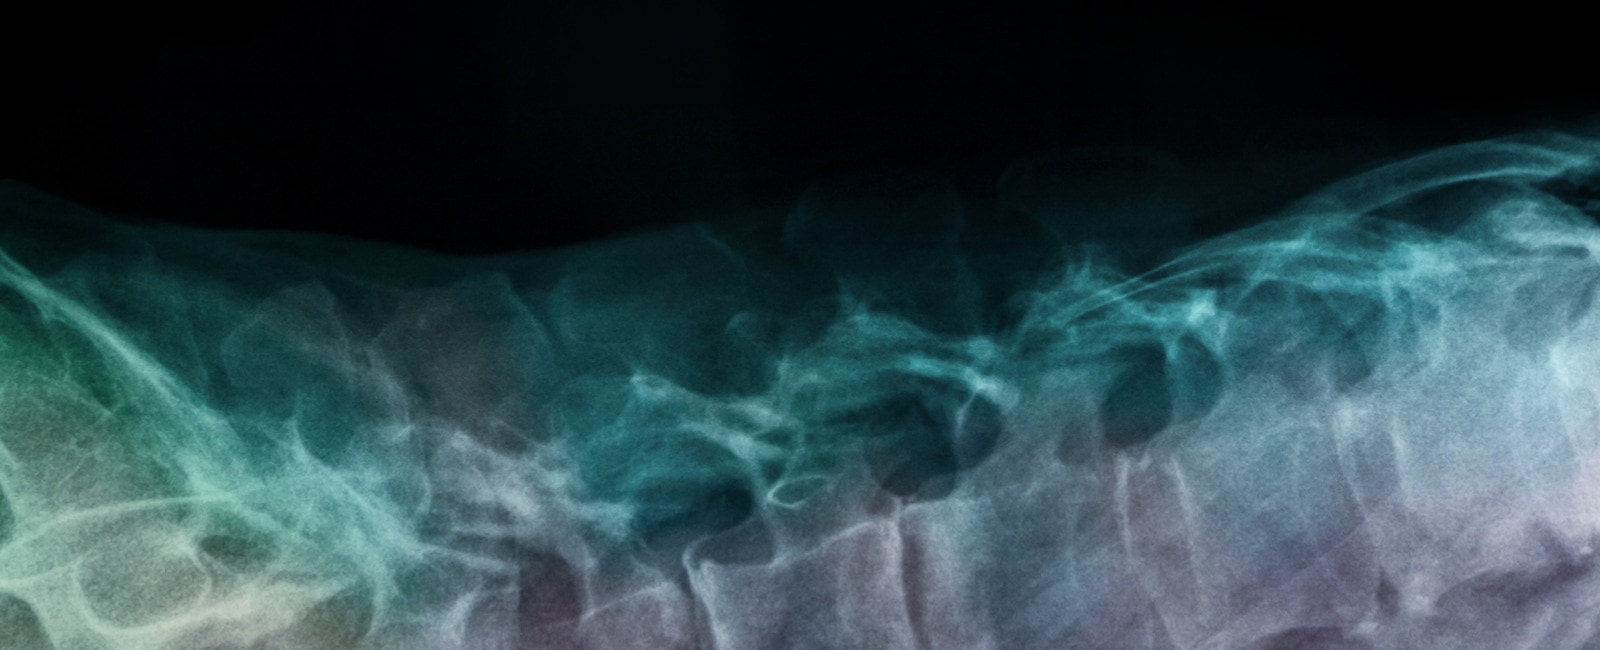

Her Spinal Column

Frida Kahlo’s spine was severely damaged following the streetcar accident in 1925. Her spine never fully healed from the trauma of the accident. In an attempt to manage the chronic pain, Frida had to wear medical corsets for the rest of her life.

In 1946, after being bedridden for four months due to severe spinal pain, Frida agreed to undergo a spinal fusion surgery in New York. The surgery, however, provided little relief. In 1950, her condition worsened and the artist was eventually admitted into the American British Cowdray Hospital in Mexico, where she stayed for nearly a year, undergoing seven operations on her spine.

X-ray of Frida Kahlo’s Spine, 1954, 2023, lightbox installation, Courtesy of the Museo Frida Kahlo Archives. © Banco de México. Fiduciario en el Fideicomiso relative a los museos Diego Rivera y Frida Kahlo.

X-ray of Frida Kahlo’s Spine, 1954, 2023, lightbox installation, Courtesy of the Museo Frida Kahlo Archives. © Banco de México. Fiduciario en el Fideicomiso relative a los museos Diego Rivera y Frida Kahlo. -